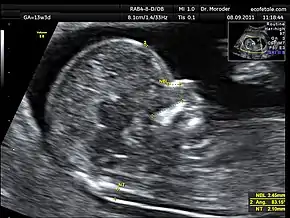

Measurements of fetal nuchal translucency, nasal bone and facial angle according to the standards of the Fetal Medicine Foundation

Nuchal scan (NT procedure) is performed between 11 and 14 weeks of gestation, because the accuracy is best in this period. The scan is obtained with the fetus in sagittal section and a neutral position of the fetal head (neither hyperflexed nor extended, either of which can influence the nuchal translucency thickness). The fetal image is enlarged to fill 75% of the screen, and the maximum thickness is measured, from leading edge to leading edge. It is important to distinguish the nuchal lucency from the underlying amniotic membrane.[8]

Normal thickness depends on the crown-rump length (CRL) of the fetus. Among those fetuses whose nuchal translucency exceeds the normal values, there is a relatively high risk of significant abnormality.